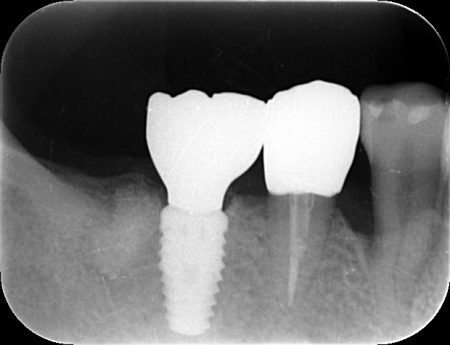

| カウンセリング | 拝見したところ、右下の奥歯(第1大臼歯)に歯根破折が確認でき、これが痛みの原因だと考えられます。 歯根破折をそのまま放置すると、歯を支える骨の吸収が進んだり周囲の歯茎が炎症を起こしたりする可能性があります。 そこで、レントゲン検査などで詳しく確認した結果、ひびは根の深い部分まで達しており、残念ながら歯を温存することは困難です。 また、その手前の小臼歯は、過去の治療で装着した詰め物の下で虫歯が再発する二次カリエスが見つかりました。このまま放置すると虫歯がさらに広がる可能性があります。 以上のことから、右下の大臼歯は抜歯後に欠損を補う治療、手前の小臼歯は虫歯の再治療が必要と診断しました。 |

患者様は「できるだけ治療期間を短くしたい」と希望されていることから、右下の第1大臼歯は抜歯即時埋入インプラントを提案しました。 抜歯即時埋入インプラントとは、抜歯と同日に人工歯根「インプラント体」を埋め込む方法です。 これにより、通常のインプラントと比べて治療期間を短縮することができます。 なおこの方法は、骨の量・質・感染の有無・歯ぐきの状態などの条件があり、すべての症例で行えるわけではありません。 また、大臼歯周囲は、歯の周りを保護する硬い歯ぐき「角化歯肉」が不足していました。 手前の小臼歯については「同じ歯の治療を繰り返したくない」とのご希望から、精密補綴治療を提案しました。 それぞれの治療内容を丁寧に説明したところ、すべての治療に同意いただきました。 まず、大臼歯の抜歯から行います。 次に、小臼歯に関しては古い詰め物を取り外し、マイクロスコープを用いて拡大視野のもとで歯の形を整えて型を採り、精度の高いセラミックの被せ物を作製・装着しました。 |